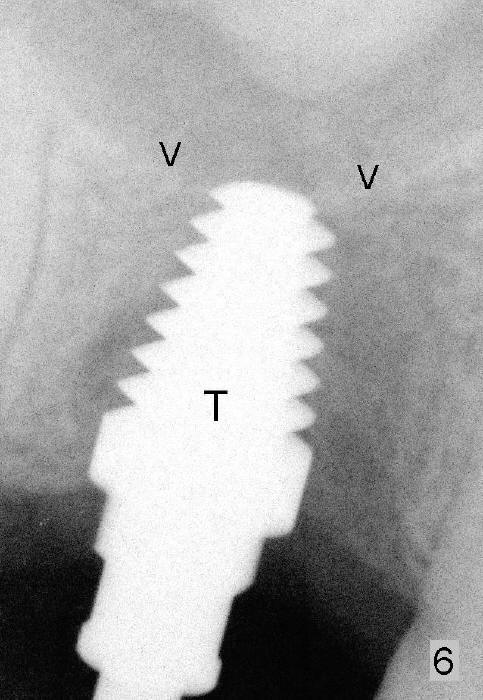

Six months and a half later, the socket appears to be empty (Fig.5) with apparently buccal plate collapse (as indicated by inset in Fig.5). The bony ridge is measured to be ~ 5 mm buccolingually using bone gauge. Osteotomy forms by bone expansion technique. In short, #15 blade is used to split the ridge (slightly lingual), followed by bone scalpels 4,5, and 6 mm, bone blades 4, 5.5 and 7.5 mm, and round tapered osteotomes 2, 3, 4 and 5 mm (Tatum Surgical). The depth is approximately 11 mm. When the last osteotome (4.5 mm round blunt) is used, it deviates too much lingually. A surgical curet is used to explore the osteotomy site. The bony wall appears to be intact except lingual. A 6x11 mm tapered tap is inserted with some resistance (Fig.6). In contrast it is difficult to engage 5.8 mm round tap into the osteotomy site. A 6x11 mm tapered implant is placed with insertion torque 40 Ncm (Fig.7). Amoxicillin is prescribed. The patient is doing fine postop, although the implant is not stable with mild tenderness. Six month post-implantation, the implant appears to have been descended (Fig.8,9, compare to Fig.7).